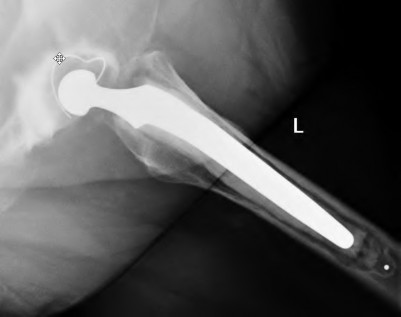

A 72-year-old male presents 2 years status post fixation of an impending pathologic right femur fracture due to metastatic renal cell carcinoma. He is minimally ambulatory due to pain. Despite radiation therapy, there has been progression of the lesion with extensive cortical bone loss, which is shown in Figure A. A proximal femoral replacement arthroplasty is performed without complications, and is demonstrated in Figure B. Which of the following is true regarding this patients post-operative course?

Figure A shows a lytic lesion of the proximal femur with an intramedullary implant. Figure B shows a proximal femoral replacement.